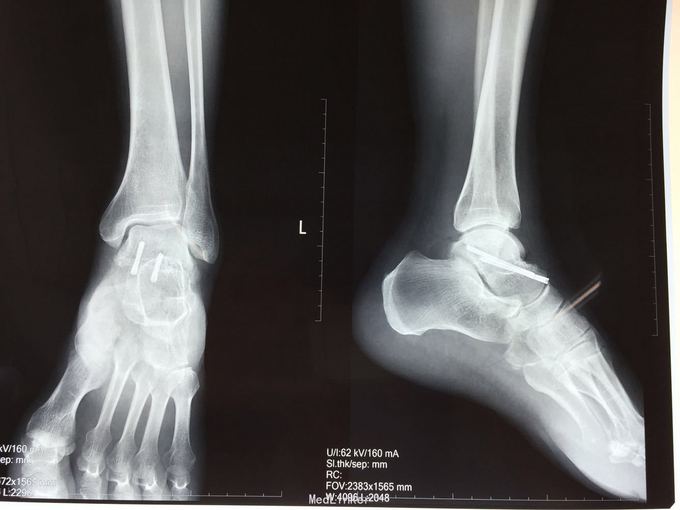

距骨骨折

患者因车祸致左足疼痛1小时入院

左足背肿胀明显,压痛

左距骨骨折